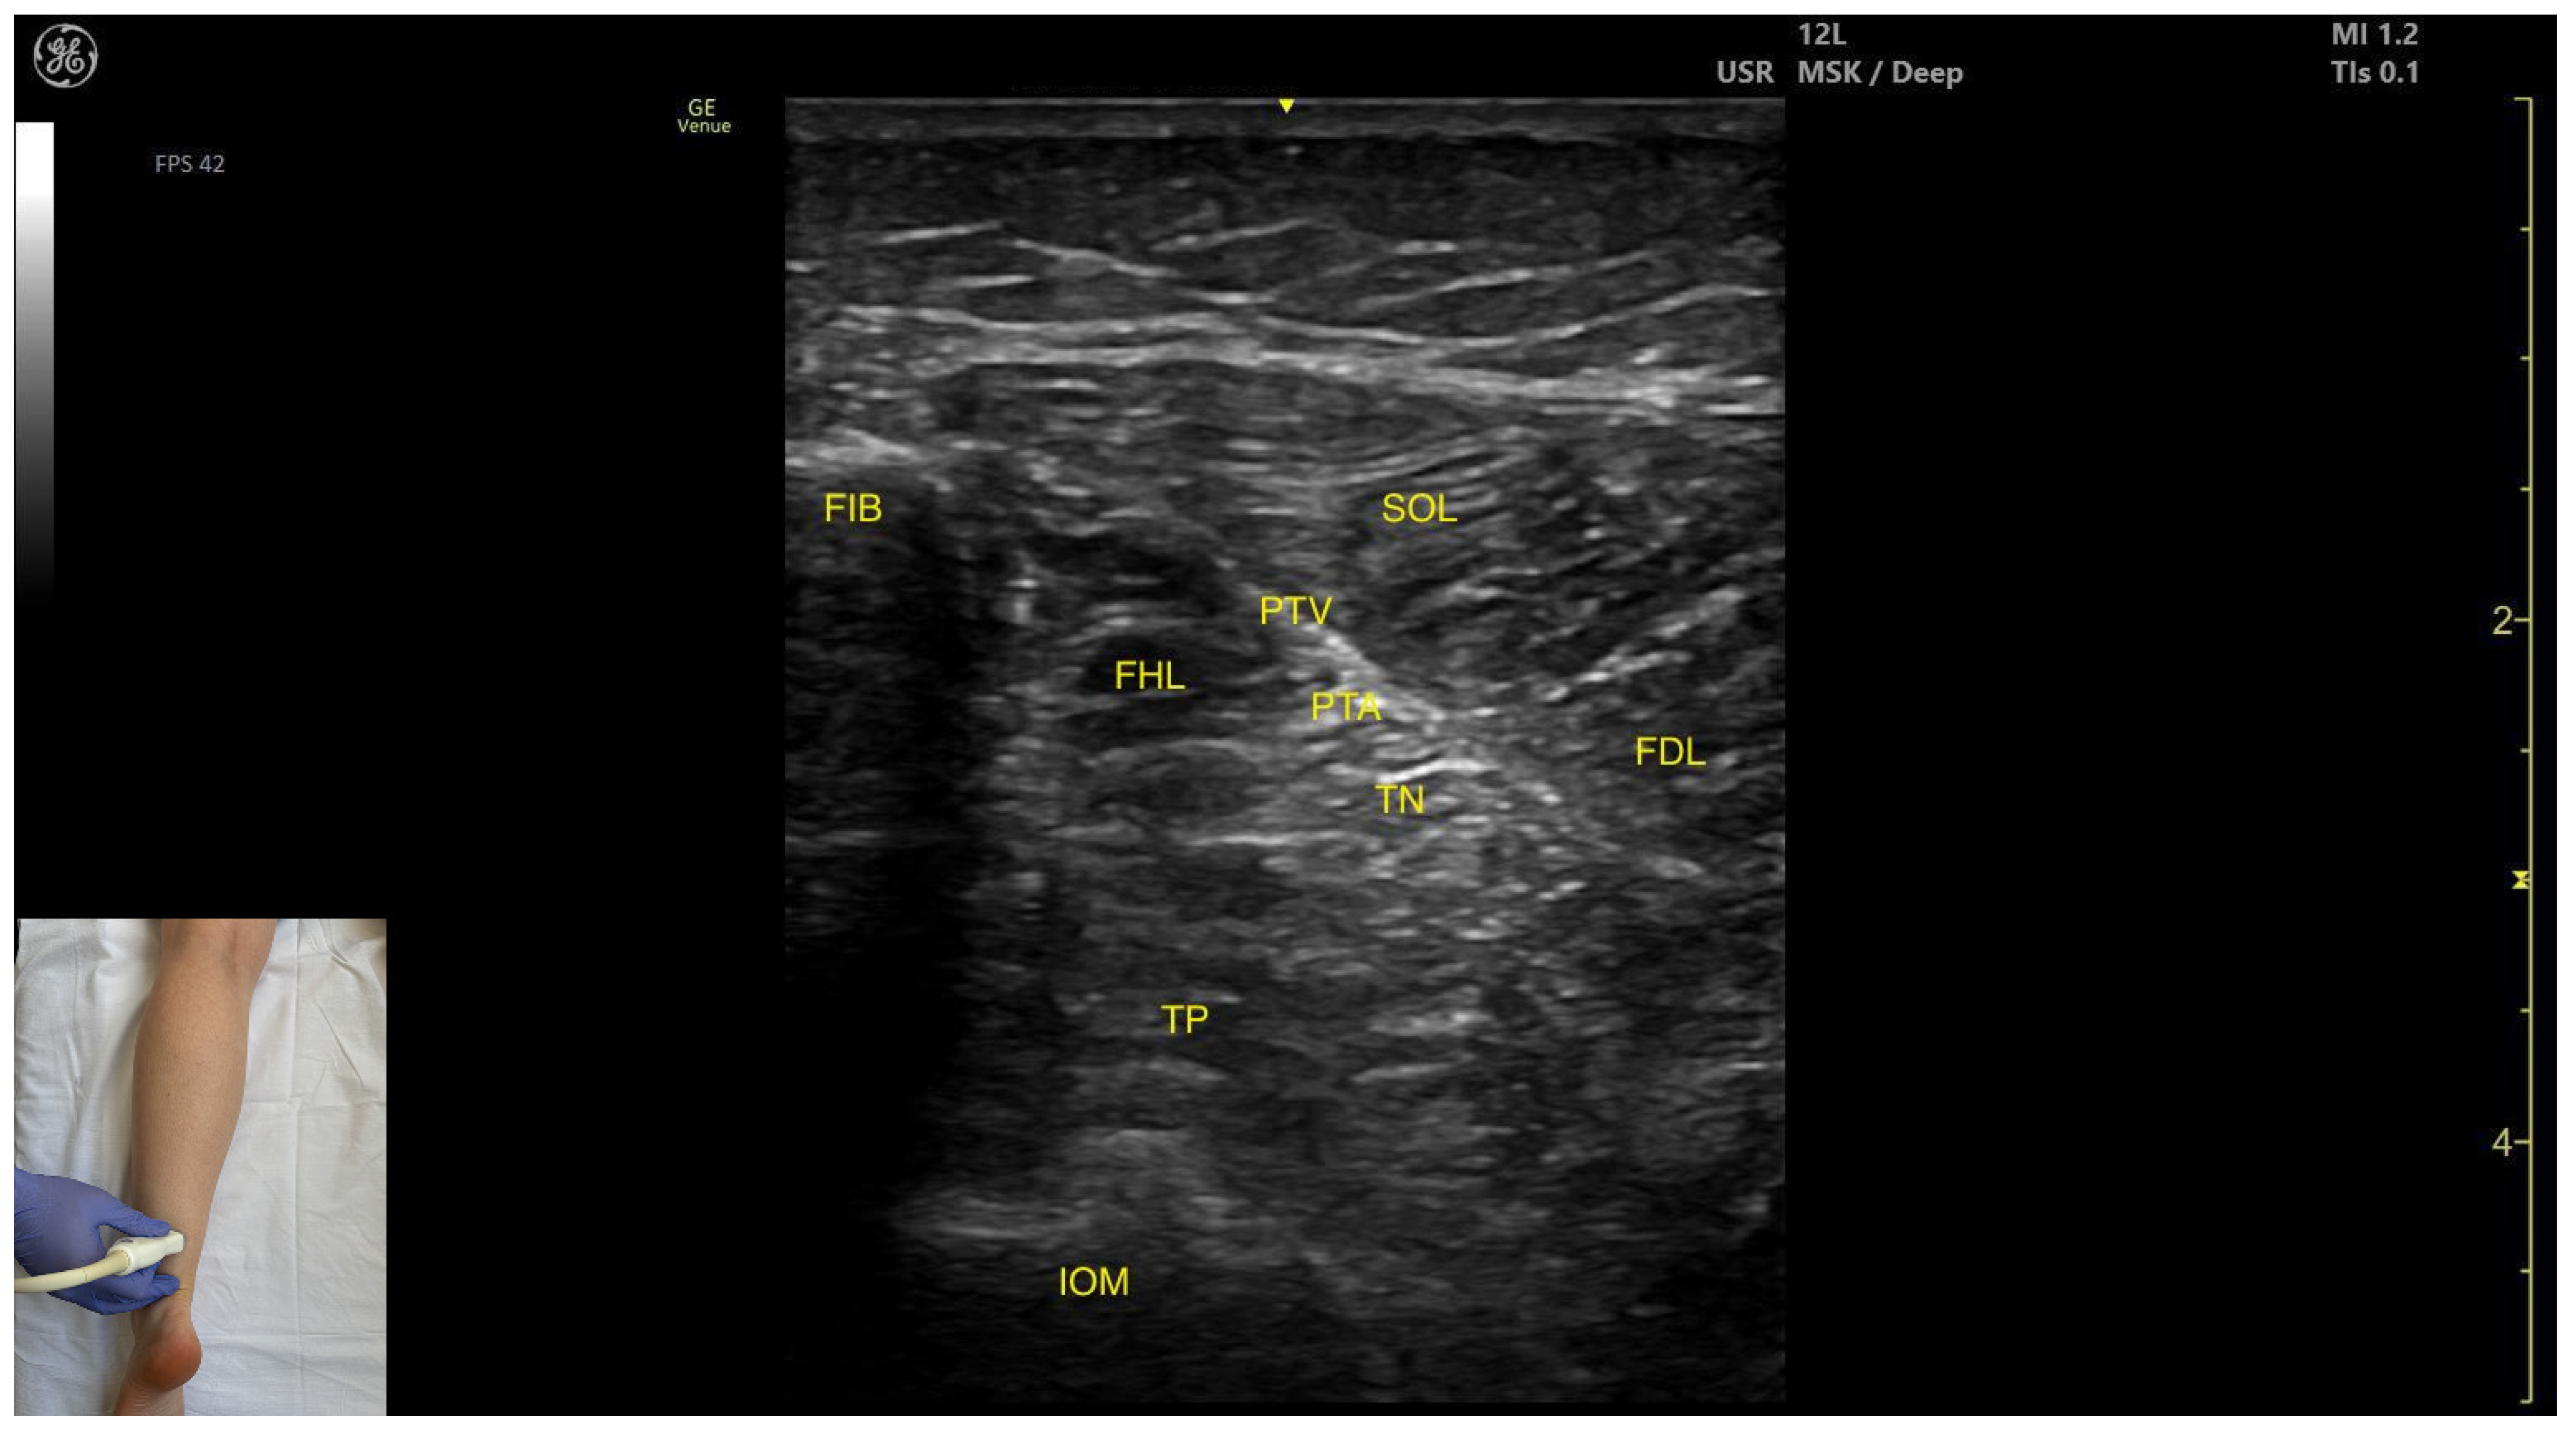

3.4. Flexor Hallucis Longus (FHL)

3.4.2. Ultrasound Identification

3.4.3. Key Ultrasound Landmarks

- Muscle morphology: It is a strong, unipennate muscle. In our clinical practice it is referred to as the “shark tail”

- Muscle position: It is located superficial to the fibular cortex. The SOL lies superficial to the FHL. Deep and medial to it lies the tibialis posterior (TP) and, deep to TP, the interosseous membrane. Medial to this region is the flexor digitorum longus (FDL). At this level, the usual anatomical relationship of the FHL and FDL is paradoxically reversed.

- Neurovascular bundle: The tibial nerve, posterior tibial artery, and posterior tibial vein lie within the intermuscular fascia between tibialis posterior, SOL, FDL.

- External fascia: The FHL has a well-defined fascia that separates it from soleus, aiding in safe BoNT-A injection. It does not have a pronounced fascia that separates it from the tibialis posterior and flexor digitorum longus.

- Dynamic evaluation: During dynamic evaluation, scanning proximally toward the knee joint, the FHL muscle thickness decreases, and it disappears from view, while the soleus thickens and the lateral head of the gastrocnemius appears superficially (Video S1). Muscle contraction is seen during flexion of the hallux at the metatarsophalangeal and interphalangeal joints, as well as during plantar flexion at the ankle joint.

| FIB | Fibula |

| TP | Tibialis posterior |

| IOM | Interosseous membrane |

| FDL | Flexor digitorum longus |

| FHL | Flexor hallucis longus |

| PTA | Posterior tibial artery |

| PTV | Posterior tibial vein |

| TN | Tibial nerve |

| Flexor Hallucis Longus | Distal third of the posterior leg, in the lateral portion | Soleus (superficial); tibialis posterior, flexor digitorum longus (deep and medial); Interosseous membrane (deep) | Transverse scan on the distal third of the posterior leg | Confirm muscle position and relations |